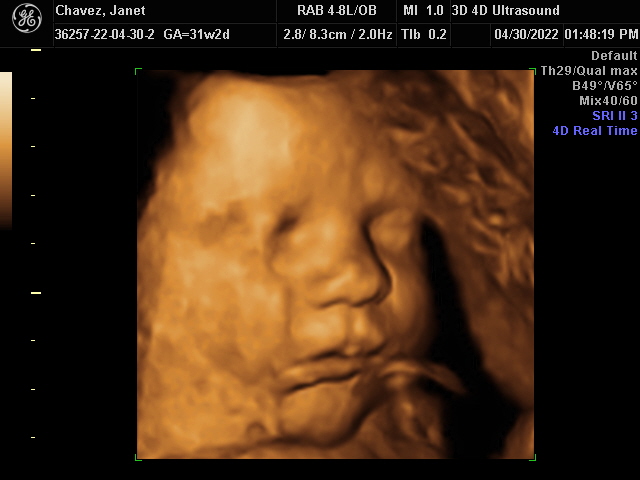

Our Gallery

Explore beautiful moments captured during our 3D and 4D sessions.